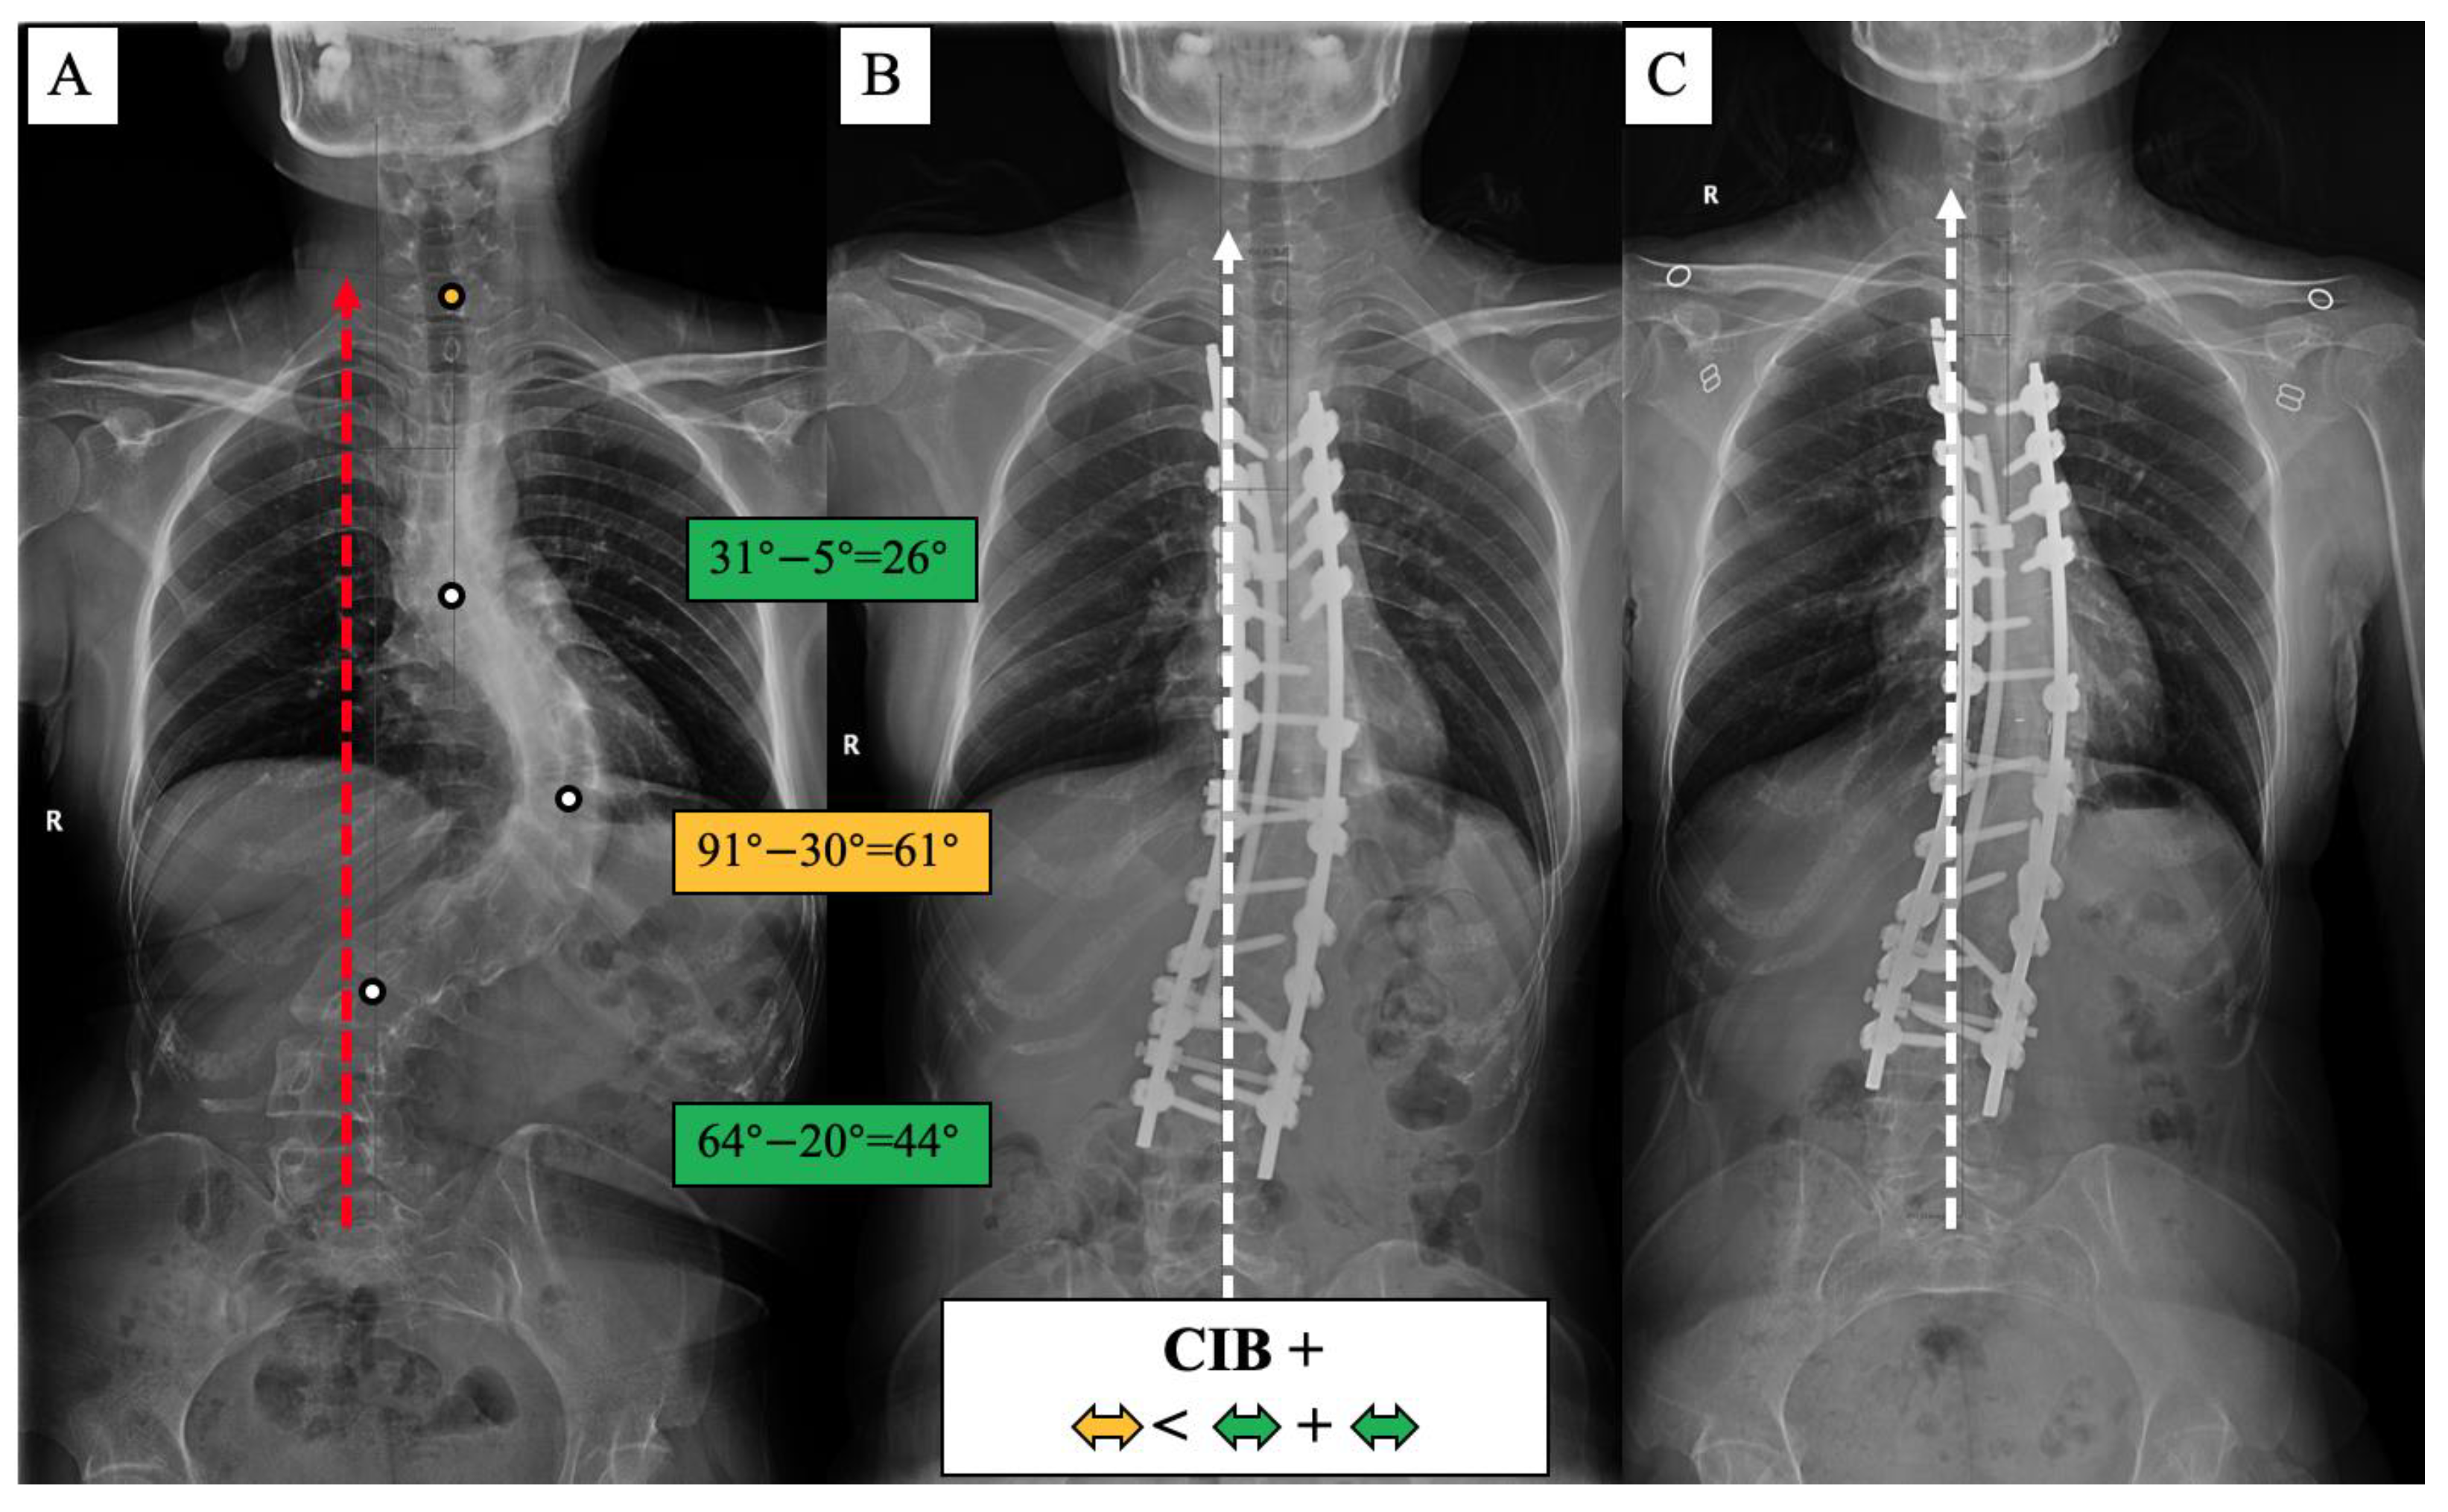

Figure 8.

CIB+ case, 21-year-old female AdIS patient ((A): preoperation, (B): postoperation, and (C): 2-year follow-up). The main thoracic curve was corrected from 91° to 30° (61° correction). The upper thoracic curve was corrected from 31° to 5° (26° correction), and the lumbar curve was corrected from 64° to 20° (44° correction). The correction rate of the main curve was less than the compensatory curves. The coronal plane balance was improved after surgery, but no further improvement could be observed at the final follow-up.